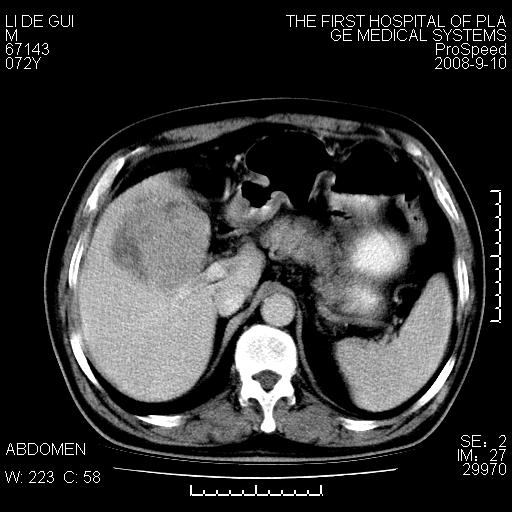

标题: CT17988:腹部肿块两年,肿块大小无变化,患者无不适,自我 [打印本页]

标题: CT17988:腹部肿块两年,肿块大小无变化,患者无不适,自我

胆囊占位性病变(黄色肉芽肿性胆囊炎?)。

考虑-----胆囊血肿机化或胆囊癌或腺肌增生症------增强

胆囊占位性病变,增强。

十二指肠的间质瘤